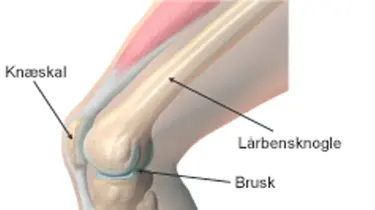

Hvorfor går knæskallen af led?

Løs knæskal er en almindelig skade, især ved sport og pludselige vrid. Knæskallen glider næsten altid mod ydersiden af knæet. Du kan være mere udsat, hvis du har:

Hver gang knæskallen smutter ud, tager brusken bagpå skade, og risikoen for smerter og hævelse stiger. Der kan derfor være god grund til at operere.

Når knæskallen har været af led, bliver ledbåndet fra knæskallen til lårbenets inderside beskadiget. Selv om ledbåndet heler sammen igen, vil det for hver gang knæskallen går af led, blive slappere og miste evnen til at holde igen på knæskallen. Derfor må man lave en rekonstruktion af ledbåndet.